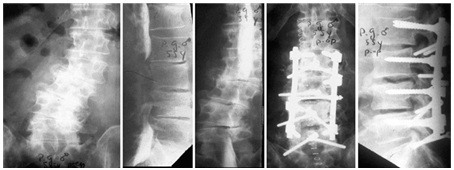

Limited Intervention by Vertebral Augmentation and TLSO & Medical TTT

- 76Years old lady attended with low and mid back pain over the last three months.

- Has a history of L4-L5 cage fusion 15 years before.

- Radiological examination shows:

- Loss of Lumber Lordosis.

- High Degree of Dorso- Lumber kyphosis.

- Wedge compression fractures at D12 &D11.

- Treatment:

- Vertebral Augmentation.

- TLOS Brace.

- Alendronate drugs for her osteoporosis (Figure 8).

Figure 8 Limited intervention by vertebral augmentation and TLSO & Medical ttt.